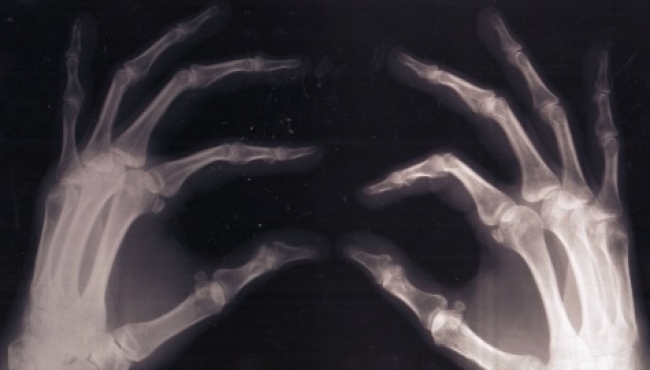

En el proceso de desgaste natural del cartílago que con el paso de los años lleva a la Osteoartritis (OA), las mujeres son las más afectadas, con una proporción de dos a uno con relación a los hombres.

En conferencia de prensa, explicó que con el deterioro del cartílago se pierde el equilibrio de las articulaciones y hay crecimiento del hueso, lo cual provoca dolor e inflamación articular.

Además del factor de género, la genética, la nutrición, la edad y los golpes (traumatismos), la obesidad, carga repetitiva de peso en articulaciones por algunos deportes, son factores que inciden en un mayor daño articular por desgaste del cartílago.

"La Osteoartritis es una enfermedad reumática que puede permanecer sin síntomas entre los 20 y 30 años, pero después de los 50 y sobretodo a los 70 años ya hay sintomatología. Con el envejecimiento y de la población este problema de salud va a ir en aumento y por cuestiones hormonales es más frecuente en mujeres", indicó.

El tratamiento debe ser con medicamentos como analgésicos y antiinflamatorios, así como con suplementos de colágeno hidrolizado que ayuda retardar el daño del cartílago.